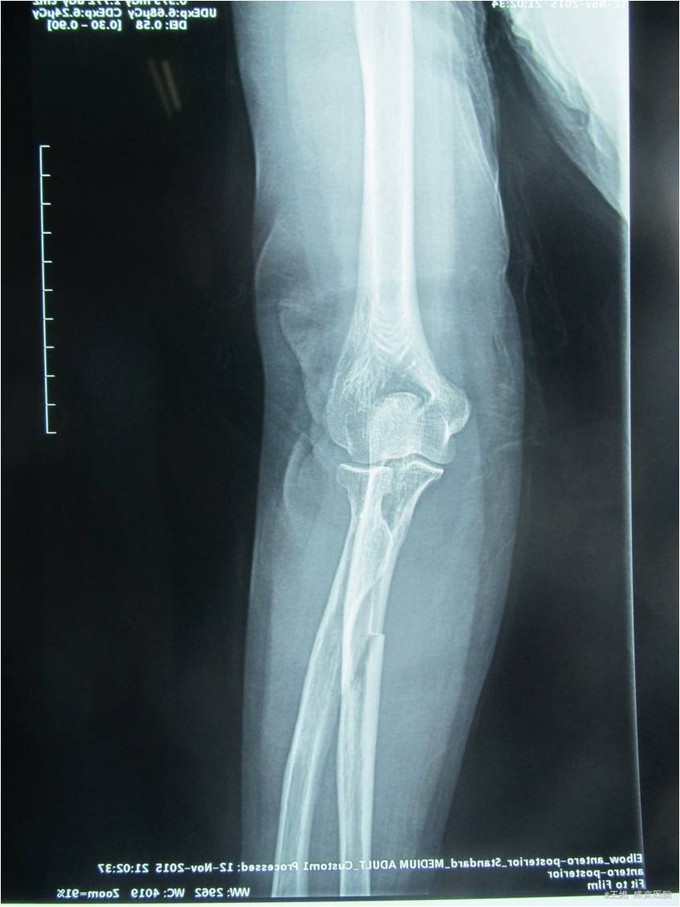

患者自诉于2015年11月12日晚6点左右走路时被汽车撞到,左前臂着地,当时左前臂疼痛,不能活动。急诊去沈阳市八院就诊,并拍片示左尺骨骨折骨折,患者及家属为求进一步手术治疗而来我院,急诊以“左尺骨干骨折”为主要诊断收入我科.病来患者饮食二便正常。

专科查体:左前臂中段肿胀,未见明显畸形,压痛(+),叩击痛(+),左肘关节及腕关节活动度良好,左手各手指活动度良好,感觉正常